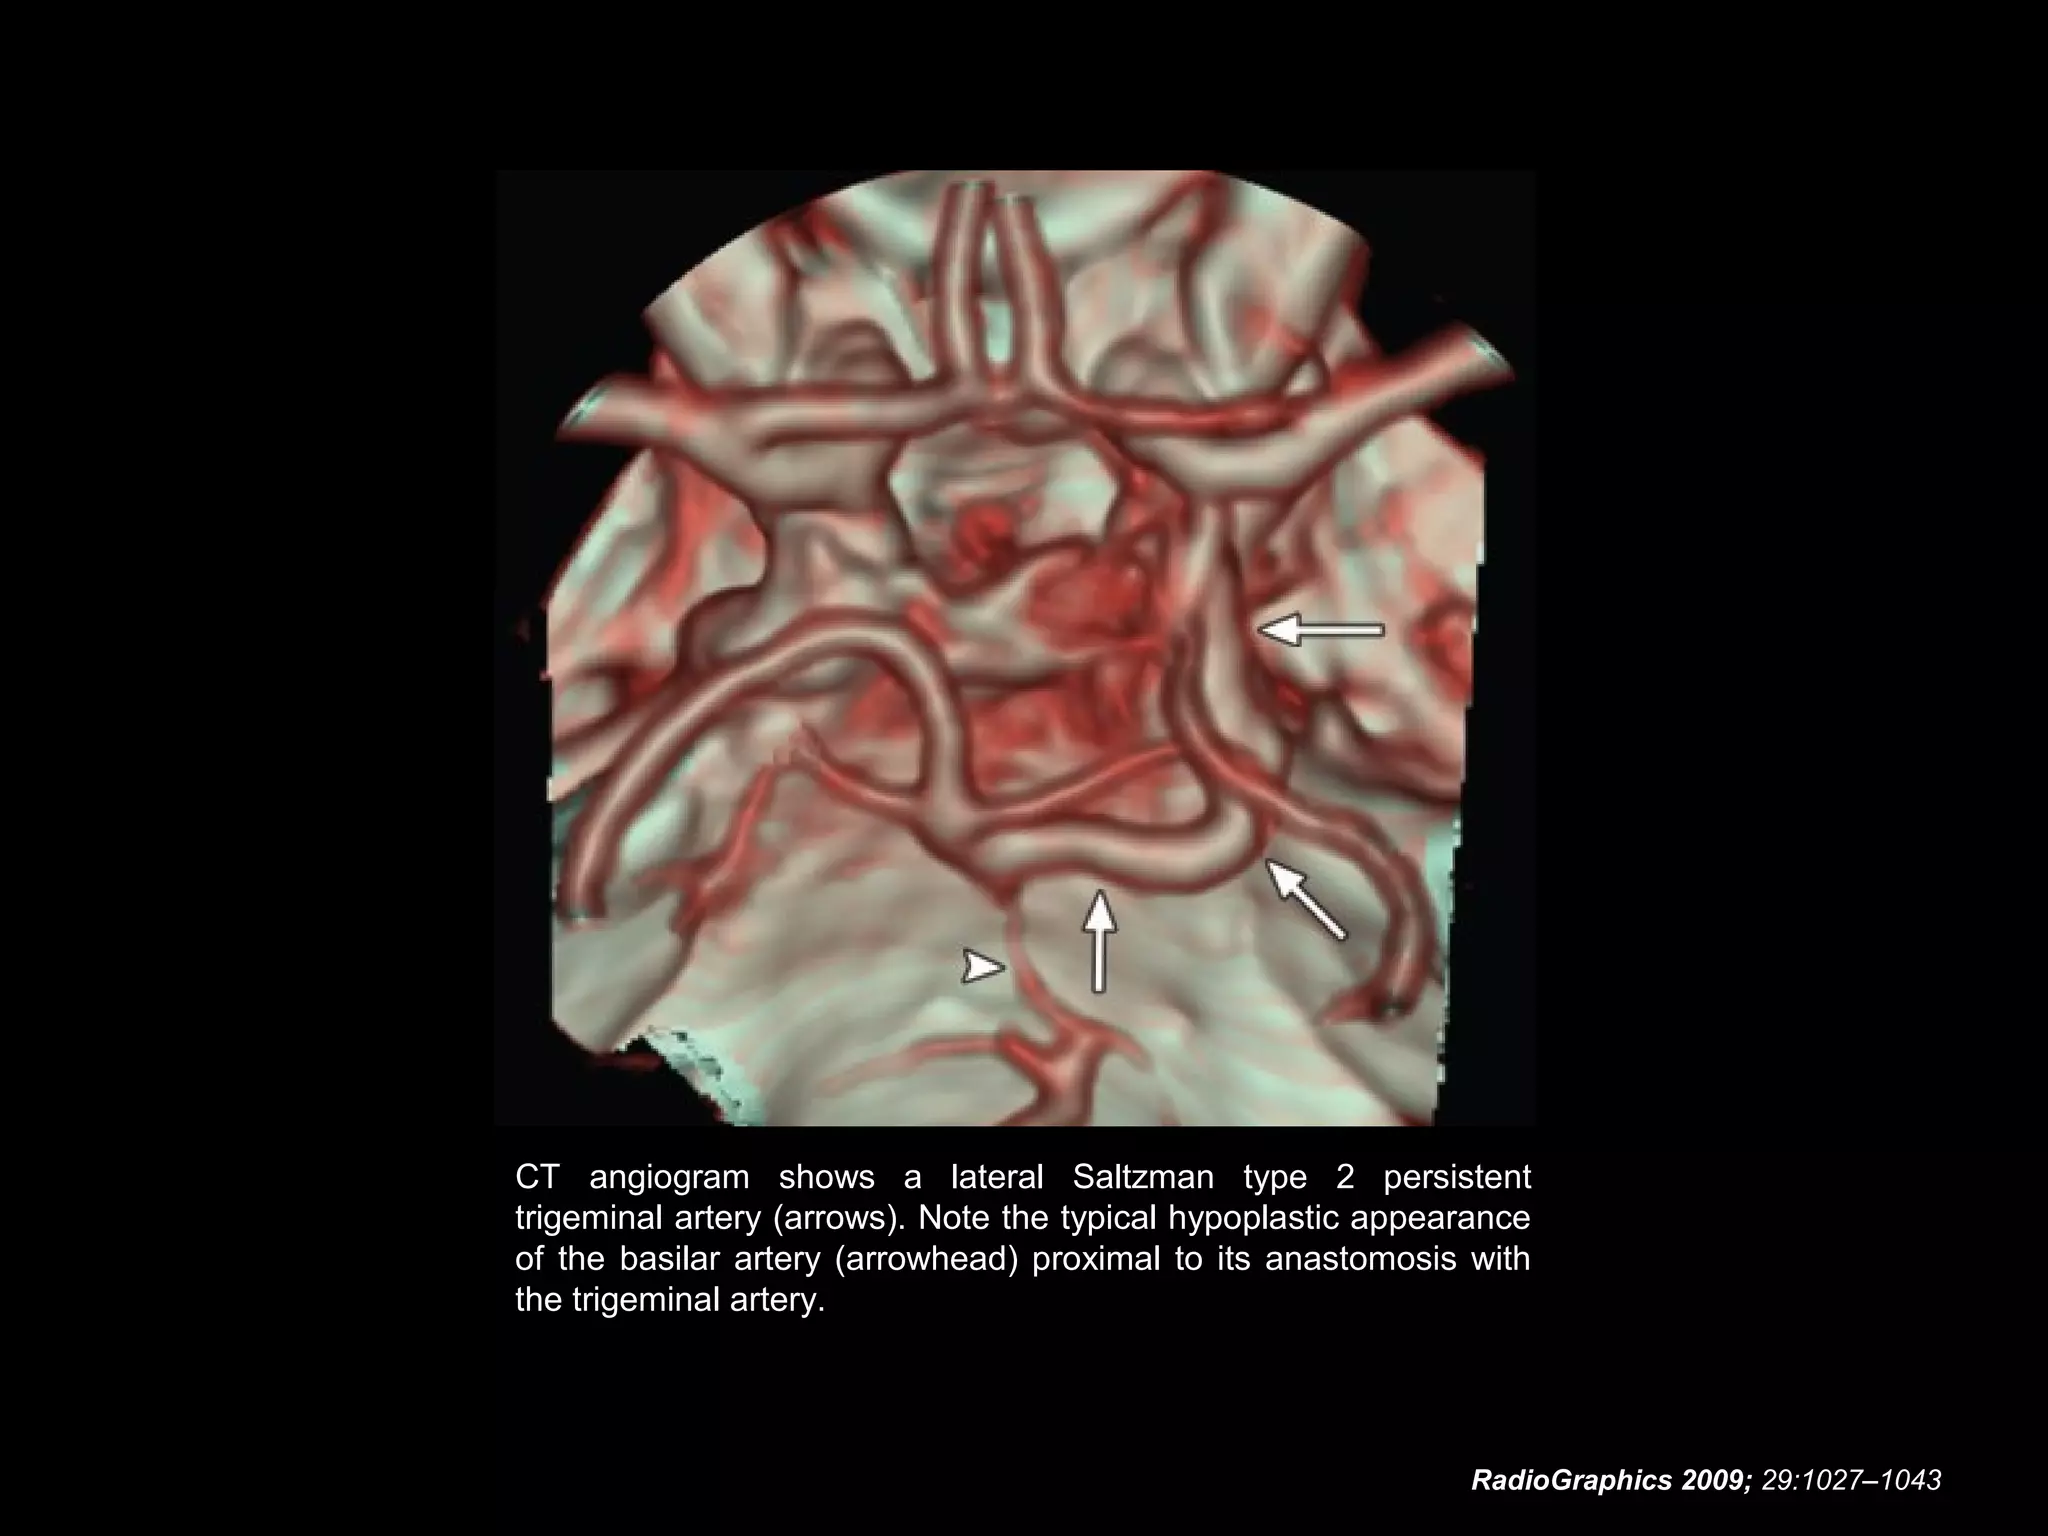

Persistent Trigeminal Artery

• A persistent trigeminal artery also is classified according

to the configuration of the ipsilateral posterior cerebral

artery:

- In the presence of a Saltzman type 1 persistent

trigeminal artery, the posterior communicating artery is

absent and the persistent trigeminal artery supplies the

entire vertebrobasilar system distal to the site of

anastomosis.

- In the presence of a Saltzman type 2 persistent

trigeminal artery there is a fetal posterior cerebral artery,

and the ipsilateral P1 segment is absent.

RadioGraphics 2009; 29:1027–1043

CT angiogram shows a lateral Saltzman type 2 persistent

trigeminal artery (arrows). Note the typical hypoplastic appearance

of the basilar artery (arrowhead) proximal to its anastomosis with

the trigeminal artery.

CT angiogram showsa lateral Saltzman type 2 persistent trigeminal artery (arrows). Note the typical hypoplastic appearance of the basilar artery (arrowhead) proximal to its anastomosis with the trigeminal artery. RadioGraphics 2009; 29:1027–1043